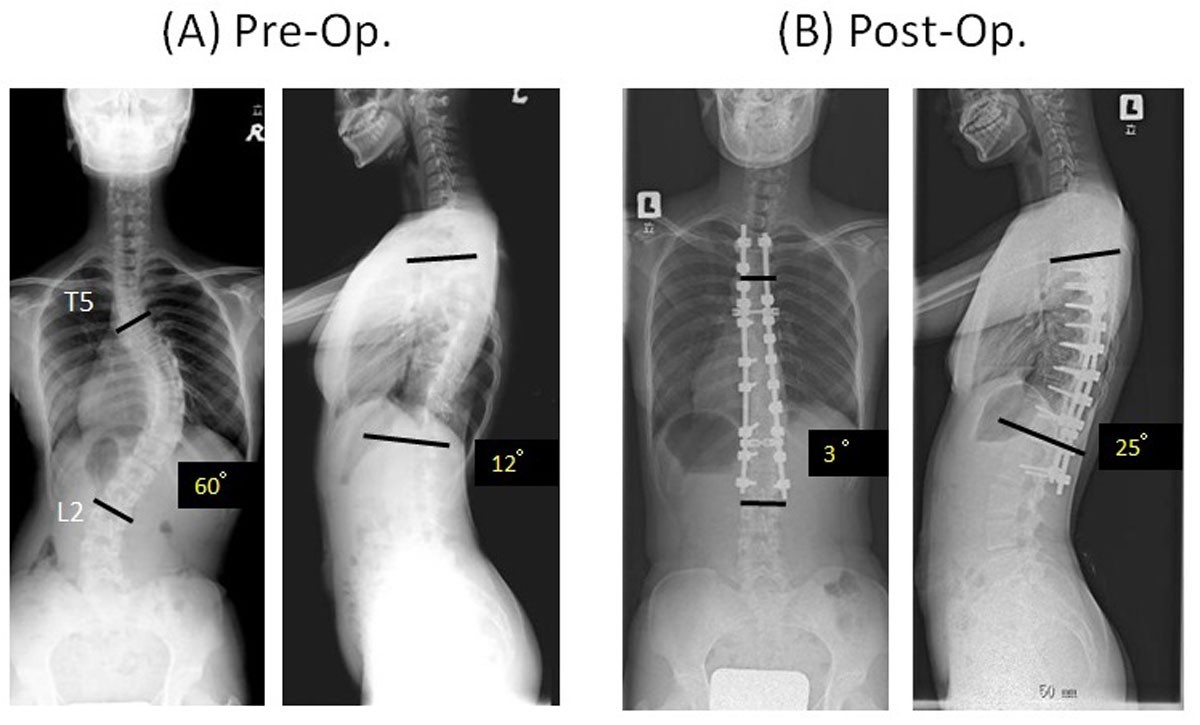

From scoliosisjournal.biomedcentral.com

A new corrective technique for adolescent idiopathic scoliosis convex Titanium Rods For Scoliosis Surgery Also known as spinal fusion, scoliosis surgery commonly involves the use of titanium metal rods that are attached to the spine with pedicle screws. For instrumented correction surgery for adolescent idiopathic scoliosis (ais), surgeons are increasingly. Harrington rod insertion is a. Most rods are made of titanium, cobalt chromium, or stainless steel. Magec growing rods are a new surgical treatment. Titanium Rods For Scoliosis Surgery.